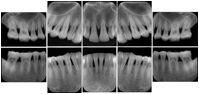

3. A dental provider wishes to capture a series of DICOM IO images for the patient’s dentition. The tooth morphology, teeth are divided into molars, premolars, canines and incisors, and a number of images for each jaw. The anatomic information was captured utilizing the triplet of schema. This standard code sequence is based on ISO 3950-2010, Dentistry - Designation system for teeth and areas of the oral cavity.

Every IO image should have anatomic information either through the primary or modifier sequence.

In most standard cases, images are oriented in structured layouts. These structured displays are useful to be shared between providers for reference purposes.

Table OO.1.1-1 shows structured display standard templates, where Viewset ID is based on the Japanese Society for Oral and Maxillofacial Radiology (JSOMR) classification provided by JIRA (Japan Medical Imaging and Radiological Systems Industries Association, www.jira-net.or.jp). Expected or typical teeth to be imaged location, region and designation codes are based on ISO 3950-2010, Dentistry - Designation system for teeth and areas of the oral cavity. For all the hanging protocols listed in OO.1.1-1, the value to use for Hanging Protocol Creator (0072,0008) is "JSOMR" and the value to use for Hanging Protocol Name (0072,0002) does not include "JSOMR" (e.g., "DL-S001A", not "JSOMR DL-S001A").